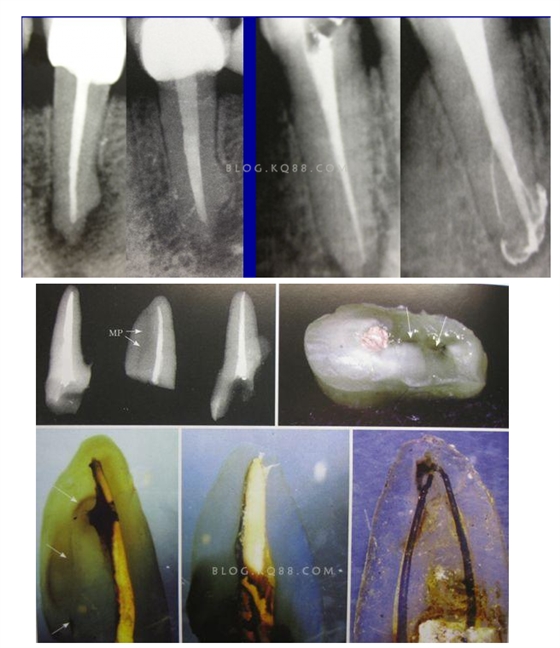

2相信有更多的根管存在 相信根管的數(shù)目比我們想象的多,根管系統(tǒng)的復雜程度比我們想象的見到的要更復雜,我們只有用盡所有努力和辦法才可能達到預期目標,對于上 牙合 6的MB2來說過去是偶爾有,現(xiàn)在是偶爾沒有,各種文獻報道的比例也不一致,我在培訓班醫(yī)生帶來的離體牙中幾乎沒有見到?jīng)]有的,臨床中也是一樣。對于尋找的方法來說,我覺得相信有才是最重要的,首先相信一定有就會想各種辦法,找到的幾率就會更多。如果有條件在顯微鏡和超聲的配合下效率會更高。

3、感染控制決定成敗 根管治療中感染控制的徹底程度直接決定根管治療的成功率,對主根管、牙本質(zhì)小管、側(cè)支根管的控制同等重要;完善根管治療后的患牙失敗主要原因是根管系統(tǒng)的頑固的感染或根尖周頑固的根管外細菌感染,當然也有可能是非細菌性因素,但根管內(nèi)的感染占主要原因。在高效率的機械預備根管時,一定要用專用的側(cè)方開口針頭的注射器大量多次的沖洗根管,次氯酸鈉要加熱后使用,并及時補充新鮮的液體到根管系統(tǒng),EDTA液體的使用可以很好去除根管預備中產(chǎn)生的玷污層,1%的CHX液體可以在30秒內(nèi)殺滅糞腸球菌,并且有延緩作用,是優(yōu)秀的終末沖洗液。超聲蕩洗清理根管的效果要優(yōu)于手工沖洗。很多醫(yī)生考慮次氯酸鈉的濃度,其實次氯酸鈉沖洗液的濃度并不重要,重要的是沖洗的時間和次數(shù),更換新鮮液體的頻率和液體是否加熱。

4、敢于否定自己 有些病例看上去似乎是完美的,但是患者就是感覺有明顯的不適感,就應該考慮是否有未處理的根管內(nèi)感染區(qū)域,分析是根管、峽部、分支、縫隙等原因后就要及時的采取措施,失敗病例的處理方法選擇非手術(shù)再治療還是手術(shù)再治療,一般首選非手術(shù)再治療,但要評估再治療的預期結(jié)果,如果非手術(shù)再治療的對患牙的創(chuàng)傷太大或預期效果不確定就考慮手術(shù)再治療,全面考慮分析后決定方法。要及時的決定下一步的處理方法。長期的反復的復診觀察是沒有意義的,最后的結(jié)果是流失患者。

5、預備到多少號結(jié)束根管預備理想的情況應該預備到多大錐度,多少號,預備后根管空間是金字塔還是埃菲爾鐵塔。專家經(jīng)過離體牙根尖切片研究發(fā)現(xiàn)根尖狹窄部遠比想象的要大,如果根管預備太小就會殘留感染物,根管的部分空間就不會預備到,殘留的感染物就會造成治療效果達不到預期目標。只有做到了充分的預備,盡可能的多沖洗才會有好的結(jié)果。